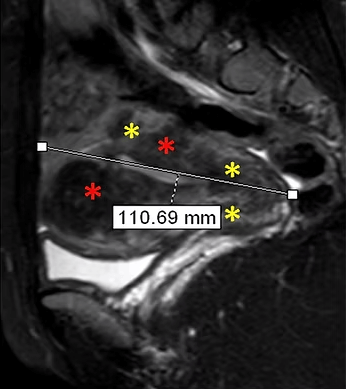

32 yaşında, kansızlık, gaz, sık idrara çıkma şikayetleri var. Emar’da 9 cm çaplı tek miyom (*) mevcut. Tek seans perkütan ablasyon sonrası miyomun belirgin küçüldüğü izleniyor. İşlemden 5 ay sonra hasta şikayetleri kalmamıştır.